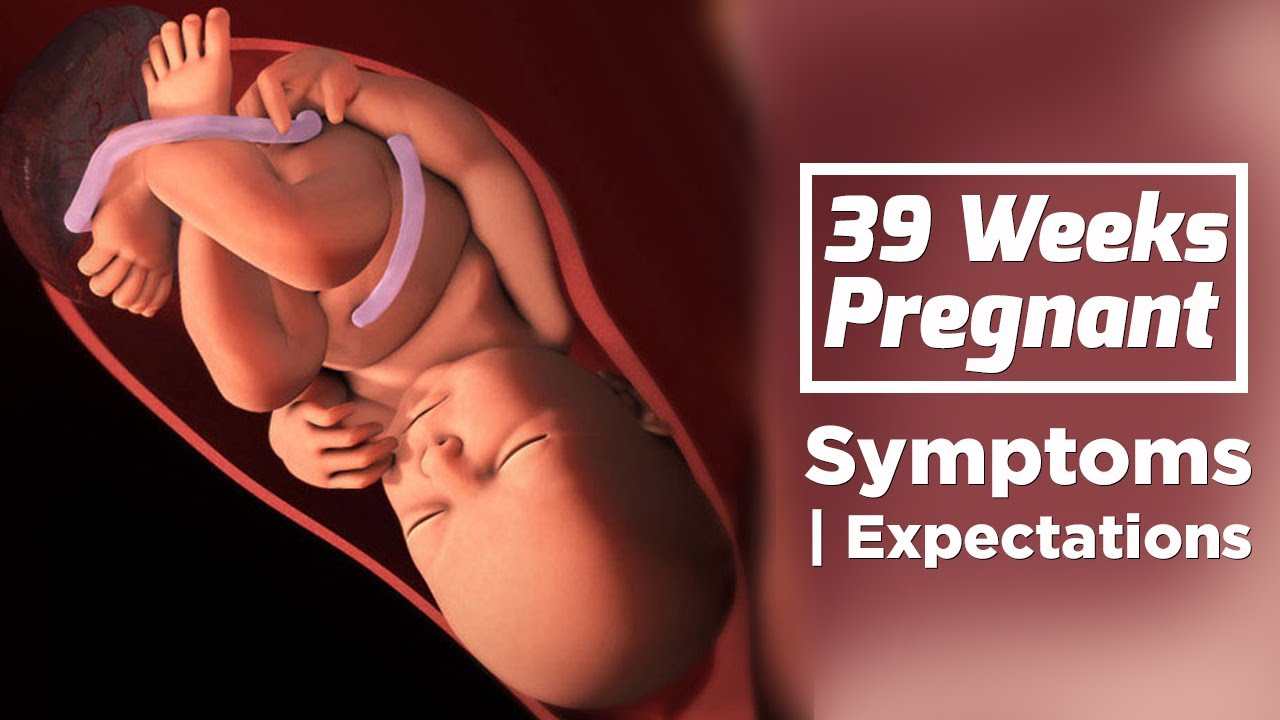

Плод 39 Недель Фото

Плод 39 Недель Фото 100 фото